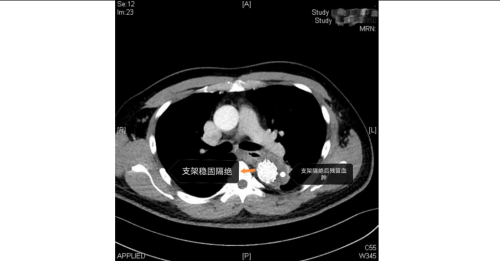

医院急诊科、麻醉手术科、外周血管介入科、急诊重症监护室等多学科团队火速响应。外周血管介入科主任、主任医师赵扬程及团队迅速评估患者病情并果断决定立即急诊手术。赵扬程指出,影像显示患者主动脉内膜严重撕裂,血流冲入血管壁形成巨大“假腔”。危急的是,夹层广泛累及腹腔主干血管,导致双下肢血管完全撕闭,下肢冰冷。此时主动脉壁薄如蝉翼,分秒间可致命破裂!同时,下肢及腹腔脏器严重缺血,如不迅速开通血管,将迅速引发肢体坏死、多器官衰竭。

手术室内,患者血压一度飙至惊人的320/150mmHg,循环濒临崩溃!麻醉团队全力稳定循环。在患者下肢几乎无法触摸到脉搏的极端条件下,外周血管介入科主任赵扬程及团队迎难而上,凭借精湛技术,精准置入支架,成功封堵主动脉内膜巨大破口,并精细重建了主动脉弓部受累的重要分支血管,恢复关键血流。这场持续近3小时的手术每一步都高风险且高度紧张,如同在死神面前进行“拆弹”。最终,这颗“血管炸弹”被成功拆除。